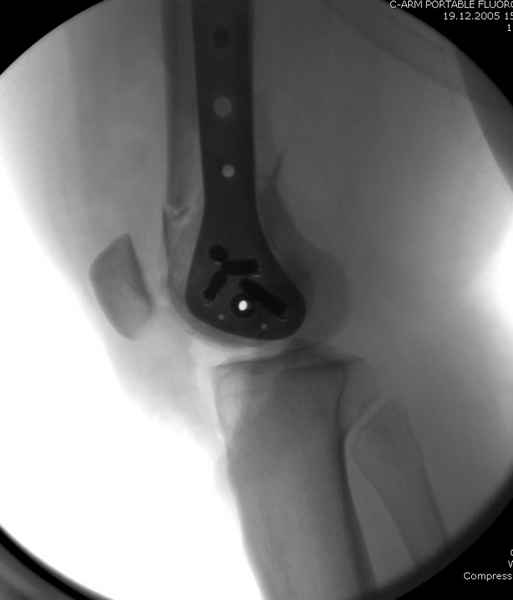

Уважаемые коллеги! От имени Алексея Смирнова всем спасибо за обсуждение. Больной прооперирован. Снимки в приложении.

При наличии различных имплантов, любые варианты: слева (полу) открытым - мининвазивным, а справа закрытым интрамедуллярным методом, его считаем более чем приемлемым для фиксации данных переломов.

Проксимальная и дистальная блокировка, независимо от техники введения штифта, ретроградно или антеградно, гарантирует сращение сегментарных переломов бедра без укорочения. Штифты диаметром 12 мм с блокировкой сверху и вниз двумя шурупами выдерживают вес 75 кг больного, что позволяет раннюю профилактику контрактур.

Из-за вариабельности установки дистальных шурупов и возможности перкутанного введения проксимально предпочитаем DePuy Polyax, хотя на сегодняшнем маркете множеств вариантов фиксации дистального бедра перкутанном методом.